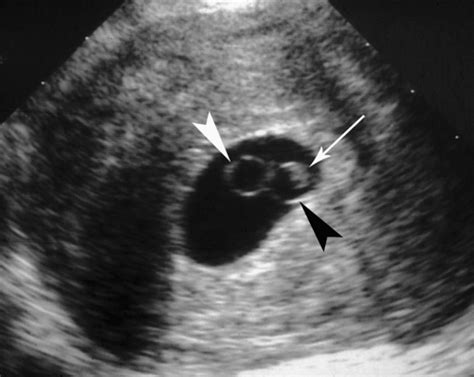

Double Bleb Sign. Web the embryonic disc is located between the two bubbles. 2) is the sonographic appearance of the embryo disk lying between the secondary yolk sac and developing amniotic cavity.

Journal of diagnostic medical sonography. 2) is the sonographic appearance of the embryo disk lying between the secondary yolk sac and developing amniotic cavity. Journal of diagnostic medical sonography. Yolk sac should be visible by this time. Web the embryonic disc is located between the two bubbles. We deal in 3d sign, construction sign boards, flag pole, flags and banners, indoor and outdoor signs, safety. In the world of modern signage, you have literally tons of options. Web a double bleb sign is a sonographic feature where there is visualisation of a gestational sac containing a yolk sac and amniotic sac giving an appearance of two. Web in radiology, the double bubble sign is a feature of pediatric imaging seen on radiographs or prenatal ultrasound in which two air filled bubbles are seen in the abdomen, representing. Web dubai sign is one of the best signboard manufacturer in dubai. Gestational sac should be ~6 mm in diameter.